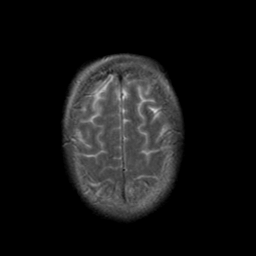

Stroke:T2-weighted MR #2 -- Slice #21

[Home][Help][Clinical] Slice 21